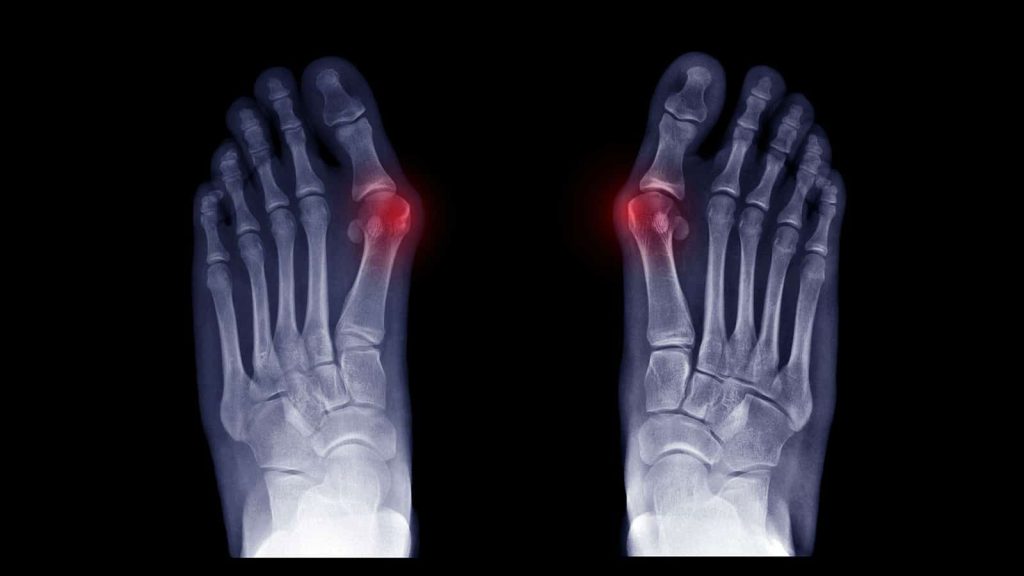

Regular checks and x-rays are recommended to prevent joint damage. Treatment options include changes in foot wear, orthotics, regular exercise, padding and active modifications such as standing or walking for long periods of time.

A bunion is a bony bump that forms at the base of the big toe where it meets the foot. The big toe may start to angle toward the second toe, and you may notice a visible lump, redness, swelling or rubbing in shoes. If you are unsure, a podiatry assessment can confirm whether you have a bunion and how advanced it is.